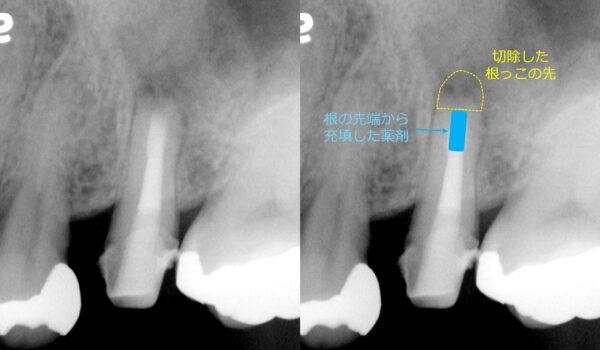

レントゲン撮影を行ったところ、左上5番目の歯の根の先に非常に大きな病変(根尖病変:こんせんびょうへん/根の先にできる炎症)が認められました。

まずは一般的な根管治療(こんかんちりょう/歯の根の中を清掃・消毒する治療)を行いました。しかし、十分な改善が見られなかったため、歯根端切除術を選択しました。

歯の根の先端を切除し、マイクロスコープ(歯科用顕微鏡)を用いて切断面を拡大観察します。その上で、根の先から逆方向に清掃・充填を行います(逆根管形成・逆根管充填)。

術直後のレントゲンでは、根の先端が切除され、先端部に充填材がしっかり入っていることが確認できました。